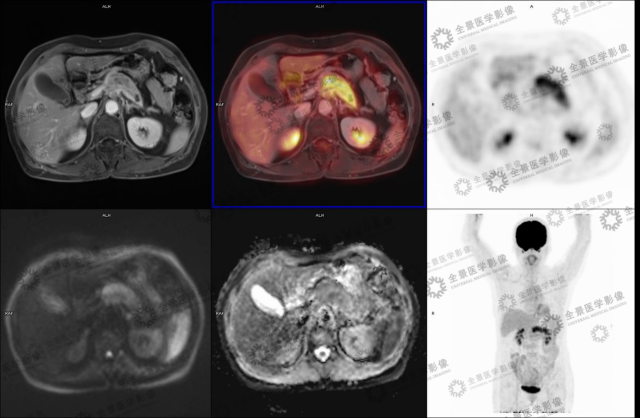

实例一

病史:女 70 岁 腹部不适,纳差半月,CT:胰腺 MT 伴小网膜囊淋巴结肿大及血管侵犯。

病灶呈延迟强化,FDG 代谢增高,考虑胰腺癌。